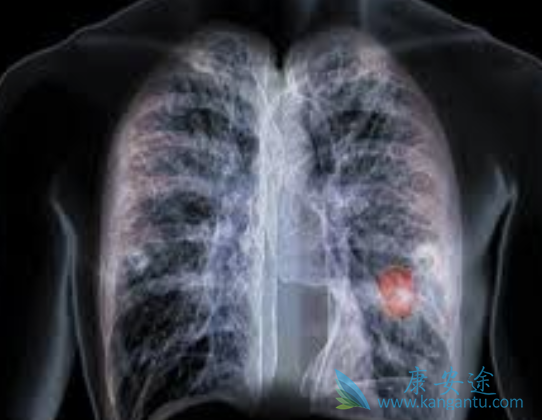

铂类是目前晚期非小细胞肺癌(non-small-celllung cancer,NSCLC)一线化疗的首选药物,多项研究表明紫杉醇、多西紫杉醇、吉西他滨及长春瑞滨等均可与铂类联用,且此类药物在无进展生存期(PFS)和总存期(OS)方面无明显差异。纳米白蛋白结合型紫杉醇(Nanoparticle albumin bound paclitaxel,nab-P)是一种无需借助溶剂的紫杉醇,大量研究证实了其对比溶剂型紫杉醇的疗效与安全性优势。吉西他滨联合顺铂治疗NSCLC也是目前国内外临床实践的热点,但尚未有研究对nab-P与吉西他滨的获益及风险进行直接比较。

本项随机II期临床研究直接比较了nab-P(单周用药)联合顺铂与吉西他滨联合顺铂在晚期NSCLC患者一线治疗中的疗效与安全性,结果表明两种方案在有效率、生存获益及安全性方面均无明显差异。但在不同组织学分类及基因突变人群中,二者的生存获益存在差异,对于体能状态较好,或EGFR突变的患者而言,使用nab-TP方案治疗可获得更长的生存期。